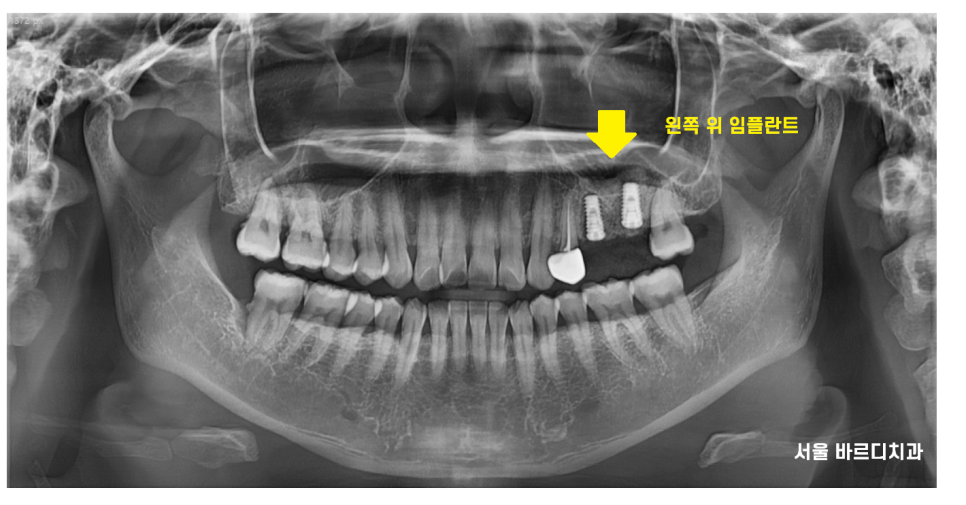

23.01.05

1월달에 덕풍동 치과에서 발치하고

잇몸뼈가 차오르기까지 기다려주었습니다.

3개월 정도 기다렸네요~~

즉시 임플란트를 심어도 되긴 하지만

내 잇몸뼈가 회복되기를 기다려주었어요.

23.04.03

3개월 뒤에 덕풍동 치과에서 임플란트 식립했습니다.

22.12.14

그동안 많이 썩은 앞에 치아도 치료하고

잇몸 치료도 하면서 기다려주었습니다.

23.11.13

사진은 완성 후 3개월 뒤 정기검진 오셨을 때

사진인데요~~

4월달에 덕풍동 임플란트 식립하고

9월에 완성해드렸어요.

위에 어금니 평균적인 완성 기간인

5개월 정도 걸렸네요~~!